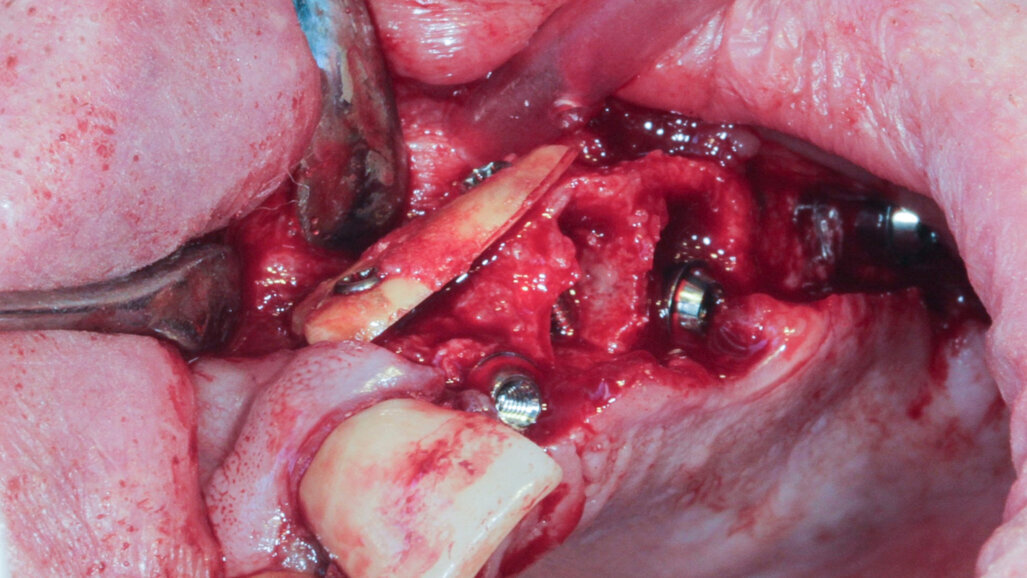

Case 2

A 62-year-old patient with a bridge from tooth #21 to tooth #27 requiring replacement, teeth #21, 23, 24 and 27 with abutments and the crown of #22, 25 and 26 missing, was treated. The ridge of tooth #22 exhibited a transverse bone insufficiency which would have allowed the placement of an implant, but the aesthetic outcome would have been unsatisfactory (Fig. 10). First, the bridge of tooth #24 was sectioned distally and the root of tooth #27 extracted. After a two-month healing period, the patient was treated with simultaneous extraction, implantation and aesthetic restoration. The bridge was sectioned distally at tooth #21, a full thickness flap was elevated and the teeth #23 and 24 were extracted, allowing the bone defect at tooth #22 to be assessed (Fig. 11). Implants were placed into sites #22, 24 and 27. The root of tooth #23 allowed us to compensate for the bone defect and achieve a satisfactory aesthetic result. The root was prepared as described. The radicular graft was fixated away from the ridge, the edges of the graft in contact with the alveolar bone (Fig. 12). The spaces between the ridge, the graft and the alveoli were filled with a synthetic, hydroxyapatite-based biomaterial, the flap was stretched and sutured around the healing abutments, an impression was taken, and a temporary prosthesis from implant #22 to 27 was made during the day by the laboratory and fitted the same evening. The stitches were removed on the tenth day and the bridge after two months to check for the successful osseointegration of the implants. The osteosynthesis screws were not removed in this case because they were not visible under the gingiva (Figs. 13 & 14). A CBCT assessment was performed after six months to check that the graft had taken successfully. Finally, our colleague fitted the definitive prosthesis.